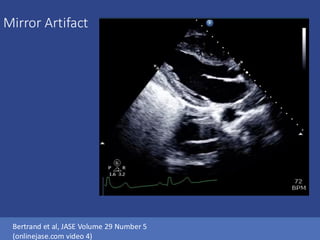

Mirror Artifact

Mirror Artifact Bertrand etal, JASE Volume 29 Number 5 (onlinejase.com video 4)